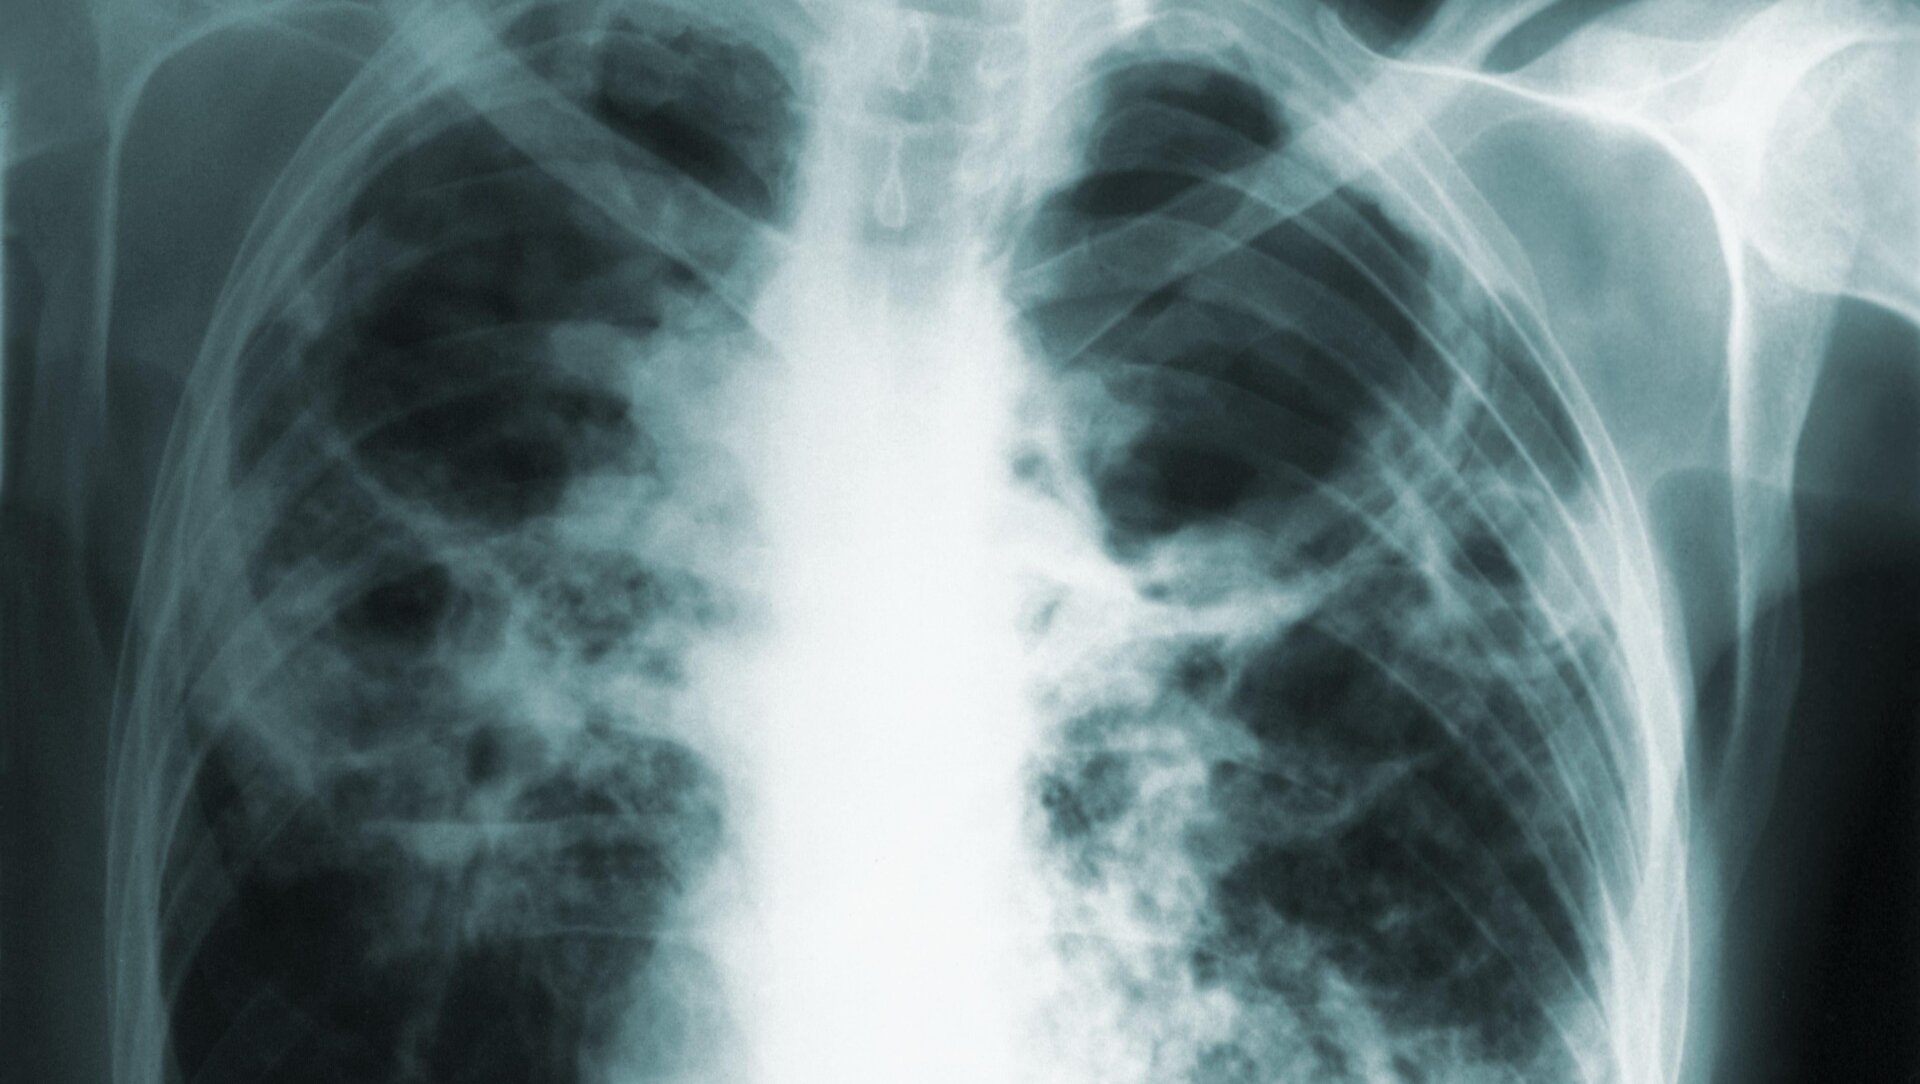

Tuberculosis, or TB, is caused by Mycobacterium tuberculosis. Many people infected with tuberculosis bacteria do not become sick, and often, the infection will enter a latent state, where levels of the bacteria remain low and people aren’t sick or contagious to others. If left untreated, though, the infection can reemerge and even become life-threatening, especially in people with weakened immune systems. Active tuberculosis typically affects the lungs, causing respiratory symptoms, but the infection can migrate to other parts of the body as well.

According to The News Tribune, the woman flouted the initial court order and subsequent ones obtained by the health department. But the last straw appears to have occurred this January. In a petition filed on January 11, the department claimed that the woman had recently gotten in a car accident. A day later, she sought care at an emergency room for chest pain and was given X-rays. The woman reportedly didn’t inform the ER of her TB status, potentially exposing them and others to the infection. Her nondisclosure even led staff to assume that her symptoms might have been caused by lung cancer. And the woman reportedly also tested positive for covid-19 at the same time.